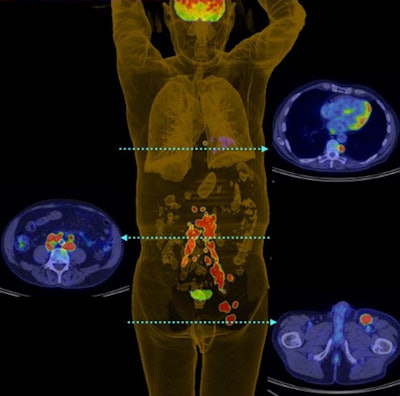

PET 3D reconstruction shows left inguinal nodal and extensive retroperitoneal and thoracic nodal metastases in patient with Merkel cell carcinoma of the left lower limb. Image courtesy of the Journal of Nuclear Medicine.Patient cohort

Patients with Merkel cell carcinoma were treated at the Peter MacCallum Cancer Centre between January 1997 and October 2010. During those years, they were imaged on either a standalone PET scanner (Quest, GE Healthcare) or on a variety of PET/CT systems (Discovery LS, Discovery STE, Discovery 690, GE; or Biograph 64/40, Siemens Healthcare). PET images were reconstructed using 3D ordered-subset expectation maximization technology.